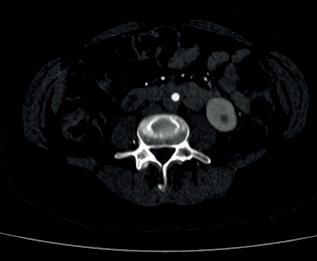

Cryoablation uses imaging guidance such as ultrasound or computed tomography (CT) scan to locate tumours. An interventional radiologist will then insert small, needle-like probes into the breast to create an ice ball that surrounds the tumour, killing the cancer cells. When combined with hormonal therapy and radiation, patients can have nearly 100% of their tumours destroyed. If the tumours do grow, patients can be treated with cryoablation multiple times to

This retrospective study assessed outcomes for 60 patients who underwent cryoablation because they were not candidates for surgery or refused surgery after consultation with a breast surgeon due to age, cardiac issues, hypertension, or currently undergoing chemotherapy for another cancer. Their tumour sizes ranged from 0.3—9cm with an average size of 2.5cm. Patients with tumours larger than

1.4cm were treated with multiple probes (one probe placement for each centimetre of disease). In a follow-up after 16 months, the recurrence rate was just 10%.

The procedures were performed with local anaesthesia or minimal sedation, depending on the eligibility and preference of the patient. The freezethaw cycle started with 5–10 minutes of freezing, followed by 5–8 minutes of passive thaw, and then 5–10 minutes freezing at 100% intensity. Patients were able to go home on the same day, following the treatment.